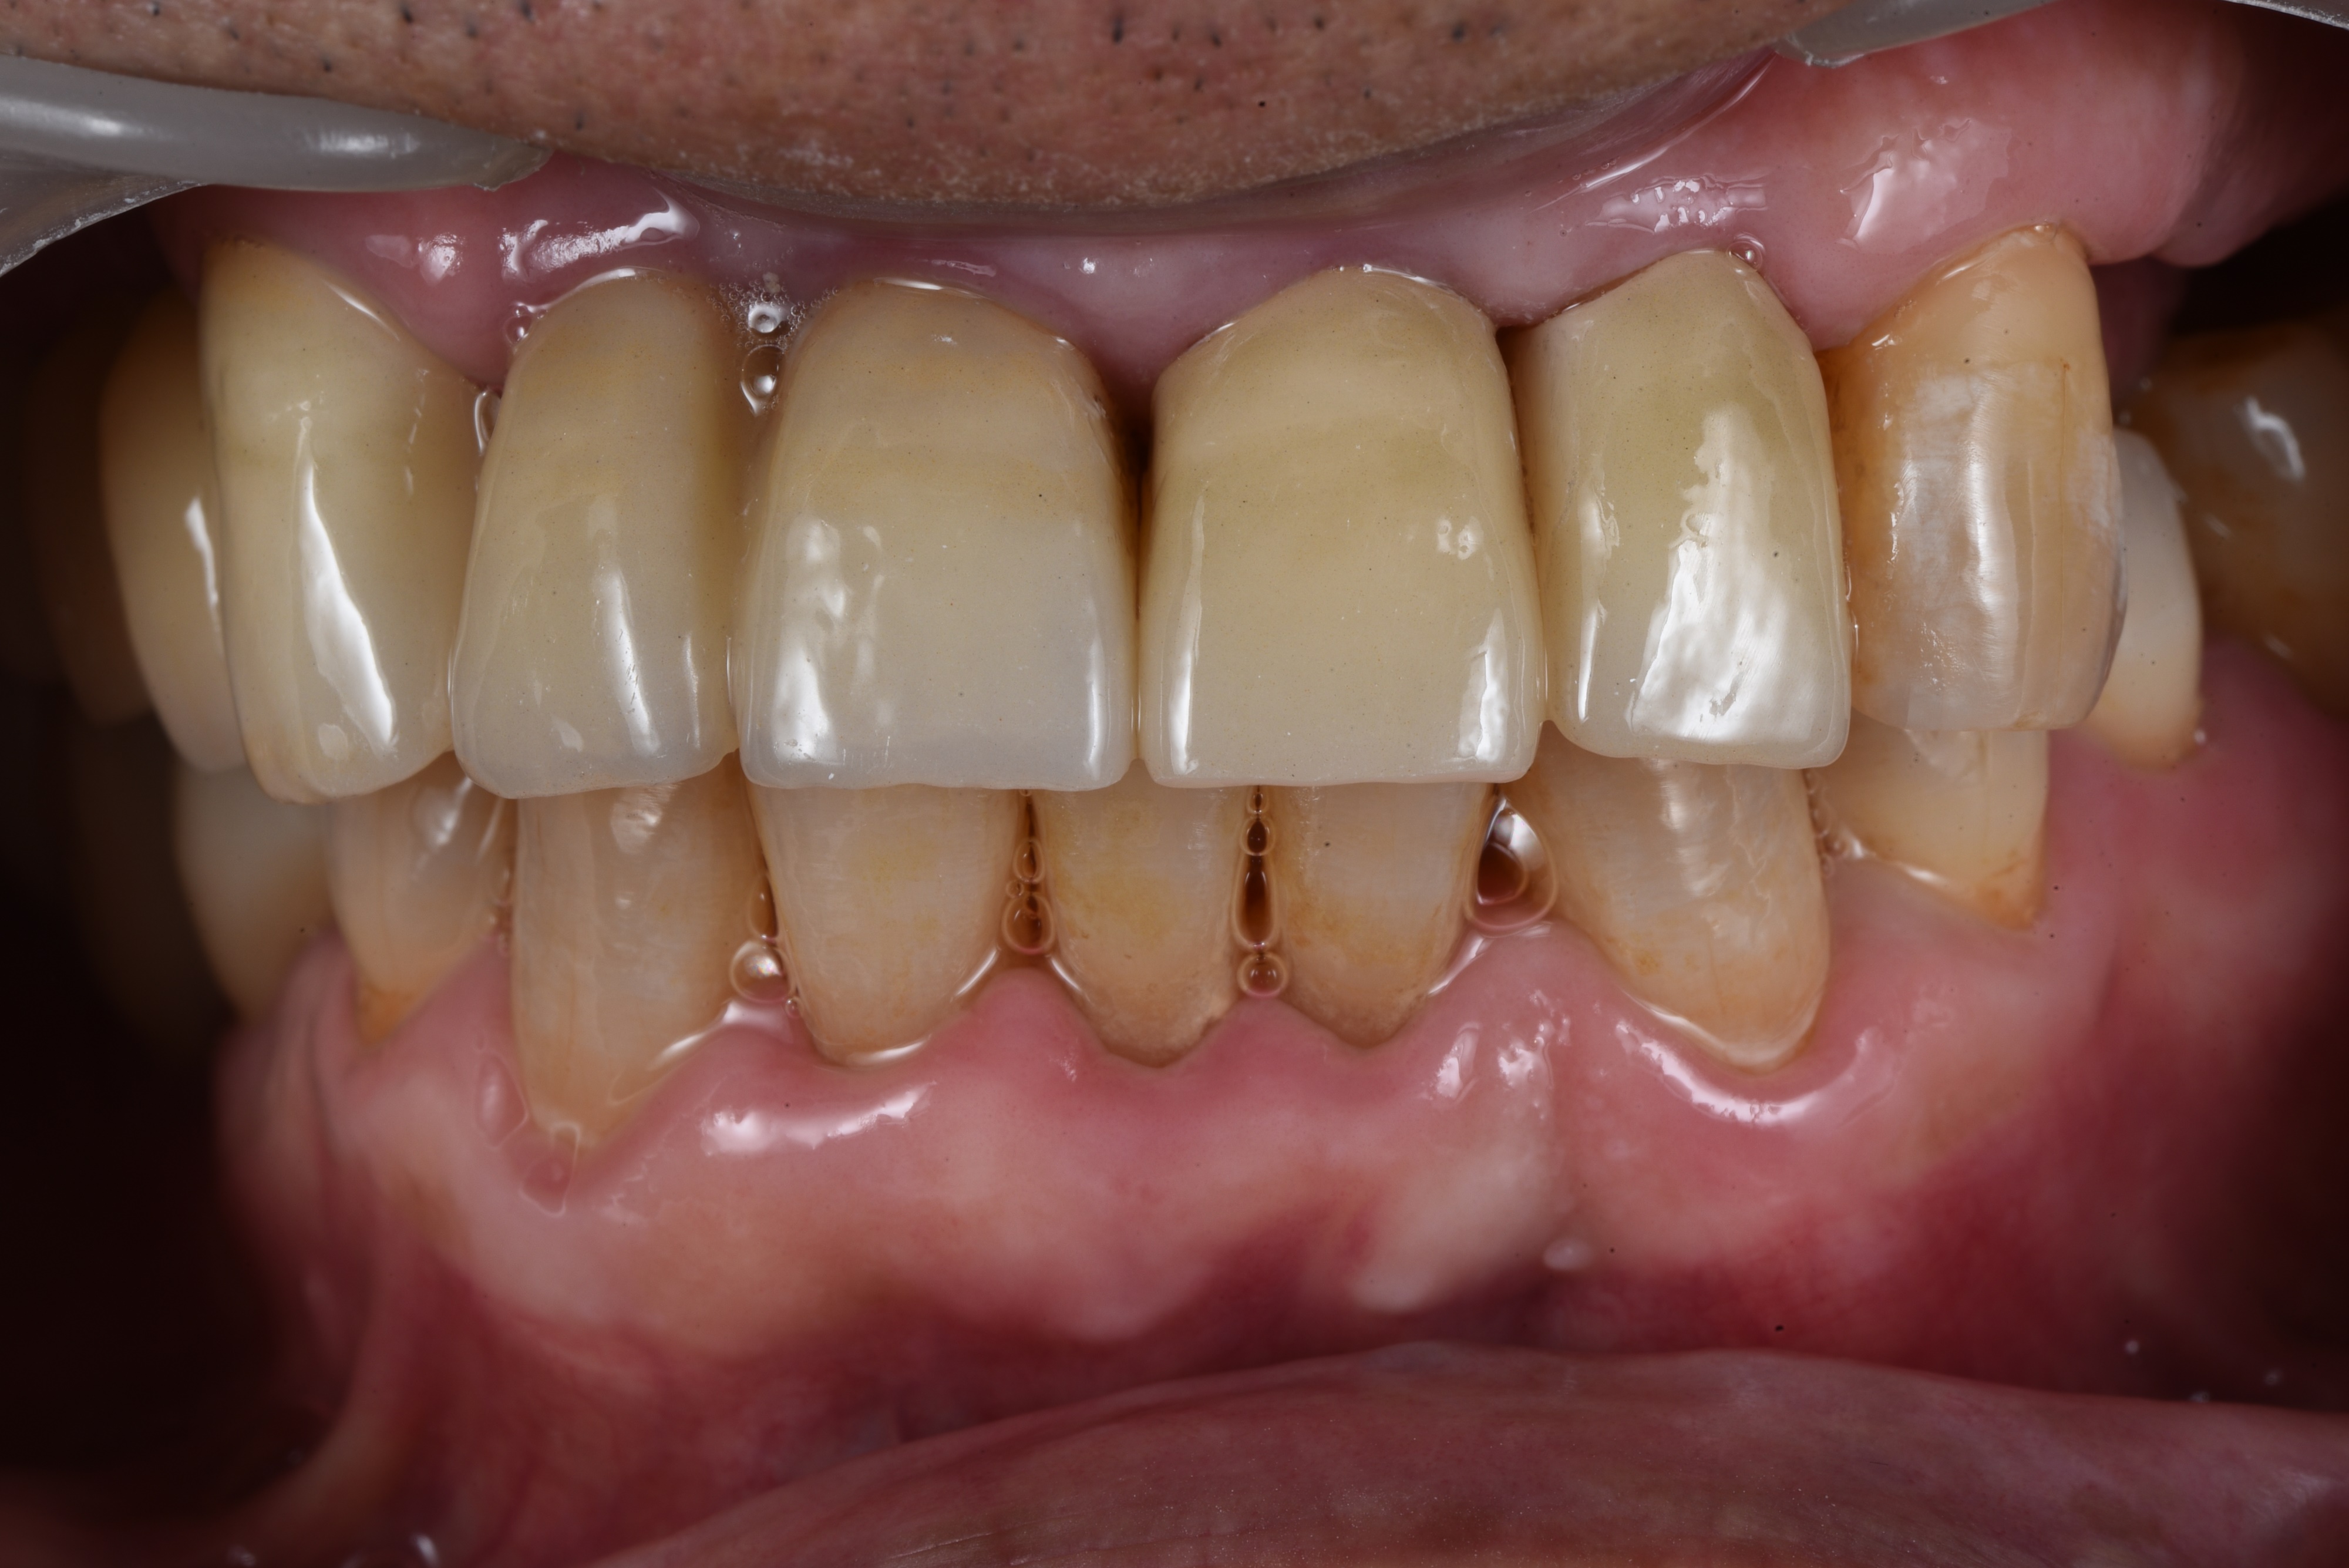

어금니 부위 10개 임플란트, 앞니 2개 임플란트를 식립하여 전체 치아를 재건해드린 사례입니다.

<임플란트 치료 후>